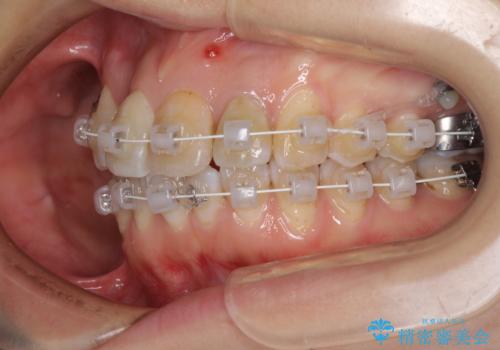

- 重なった前歯を邪魔に感じ、汚れも溜まりやすいことを気にして来院された患者様です。

右上前から2番目の歯が内側に転位しているため、上顎の正中は右にずれていました。

右上4番目の歯を抜歯し、上顎裏側に補助装置を装着して左の歯列全体を後方に移動させながら、正中を合わせるようにして行くこととしました。

内側に転位していた歯はきれいに歯列に収まり、清掃性が著しく改善しました。

元々神経の失活してしまっている前歯2本は変色が目立つようになってきたため、今後セラミッククラウンによる補綴治療を行う予定です。